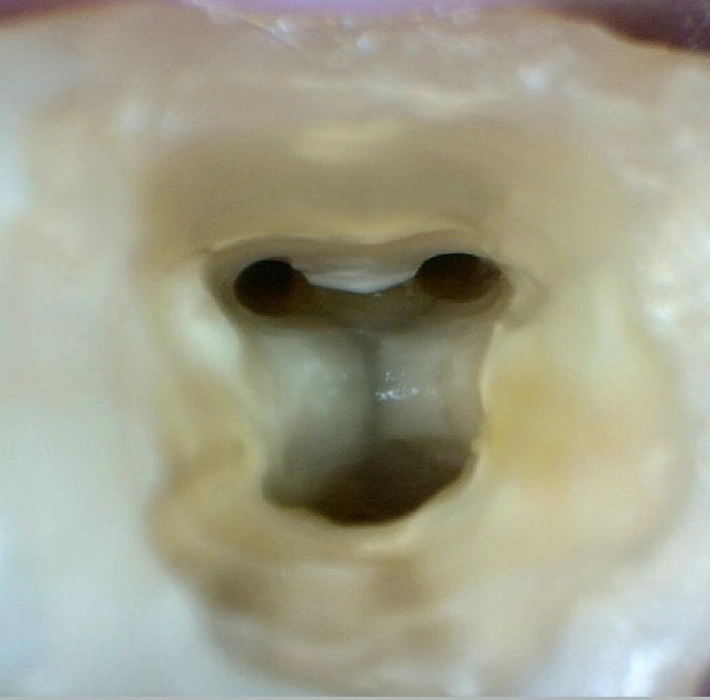

Tratamento Endodôntico (Canal)